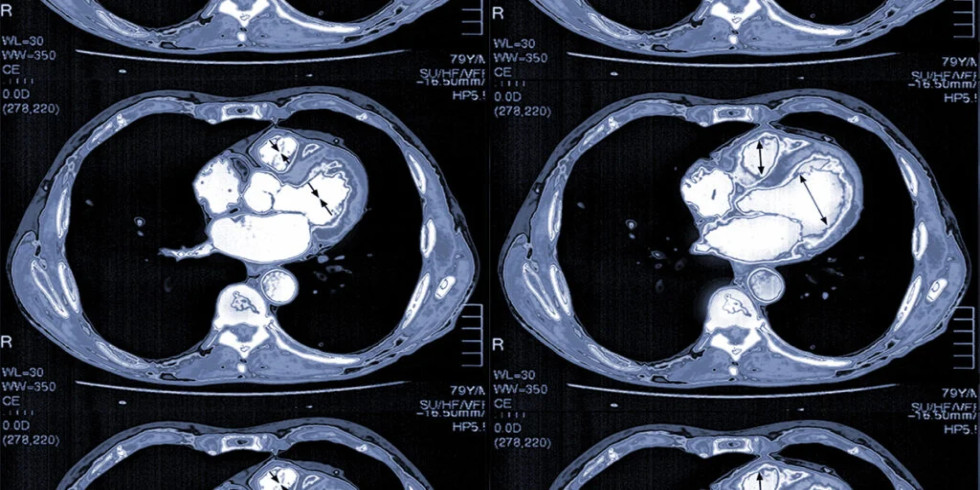

CT scan images of the coronary arteries with dye Forward Integration Agent

CT scan images of the coronary arteries HISTORY